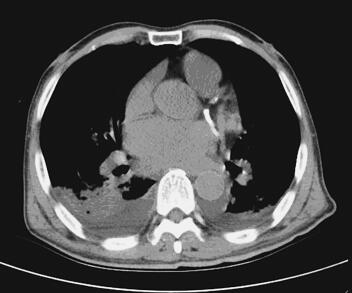

诊治经过:入院后予以吸氧、强心、利尿、抗感染、解痉、平喘、化痰、抗血小板、稳定斑块、营养心肌及改善心肌供血等相应治疗,并给予胺碘酮控制心室率,心室率控制在75~120次/分,气促、胸闷症状得到明显缓解,各项生命体征逐步正常稳定,肺部干湿性啰音逐步减少消失。心脏彩超:左右心房及左心室扩大;左心室弥漫性收缩功能减低;少量二、三尖瓣反流;主动脉瓣退行性变并少量反流;主动脉硬化。肺部CT(图2):双肺纹理增粗、模糊,双肺背侧见大片斑片状渗出及实变影;气道大致通畅,肺门未见明显增大,纵隔内见多发肿大淋巴结。两侧胸腔积液(图1、图3),两下肺膨胀不全。冠状动脉见条形致密影。查血PCT高达84.14ng/ml,入院初始予以头孢哌酮-舒巴坦钠抗感染,PCT逐渐下降,但仍有反复寒战、发热症状,体温波动在37~38℃。直至第4天血培养结果提示金黄色葡萄球菌MRSA(+)。依据药敏试验结果改用环丙沙星和盐酸米诺环素,连续用3天,患者仍有发热、寒战,体温依然波动在37~38℃。遂停用环丙沙星,加用替考拉宁,此后,患者体温明显下降并很快降至正常范围,发热、寒战等症状亦消失。最终病情好转稳定出院。

图1 肺部CT:两侧胸腔积液